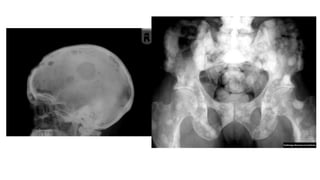

Hyperparathyroidism:

🠶Excess parathyroid hormone secretion mobilizes

calcium from the bones, resulting in a decrease in bone

🠶Primary: hyperplasia or a tumour of the parathyroid

glands

🠶Secondary: chronic renal failure

🠶A generalized loss of bone density, with loss of the

differentiation between cortex and medulla. The

trabecular pattern may have a fine lacework

appearance. With advanced disease there may be

marked deformity of the skeleton.

🠶The hallmark of hyperparathyroidism issubperiosteal

bone resorption, particularly at the radial side of the

middle phalanges and at the tips of the terminal

phalanges.

🠶There may also be resorption of the outer ends of the

clavicles.

🠶Soft tissue calcification, vascular calcification and

chondrocalcinosis:more in the secondary type

🠶Brown tumours: seen more in primary type. Lytic lesions,

single or multiple, of varying size and may be expensile.

They occur most commonly in the mandible and pelvis.